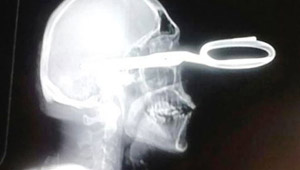

جاء للطبيب والمقص منغرز في رأسه يشكو من مشكلة بسيطة!